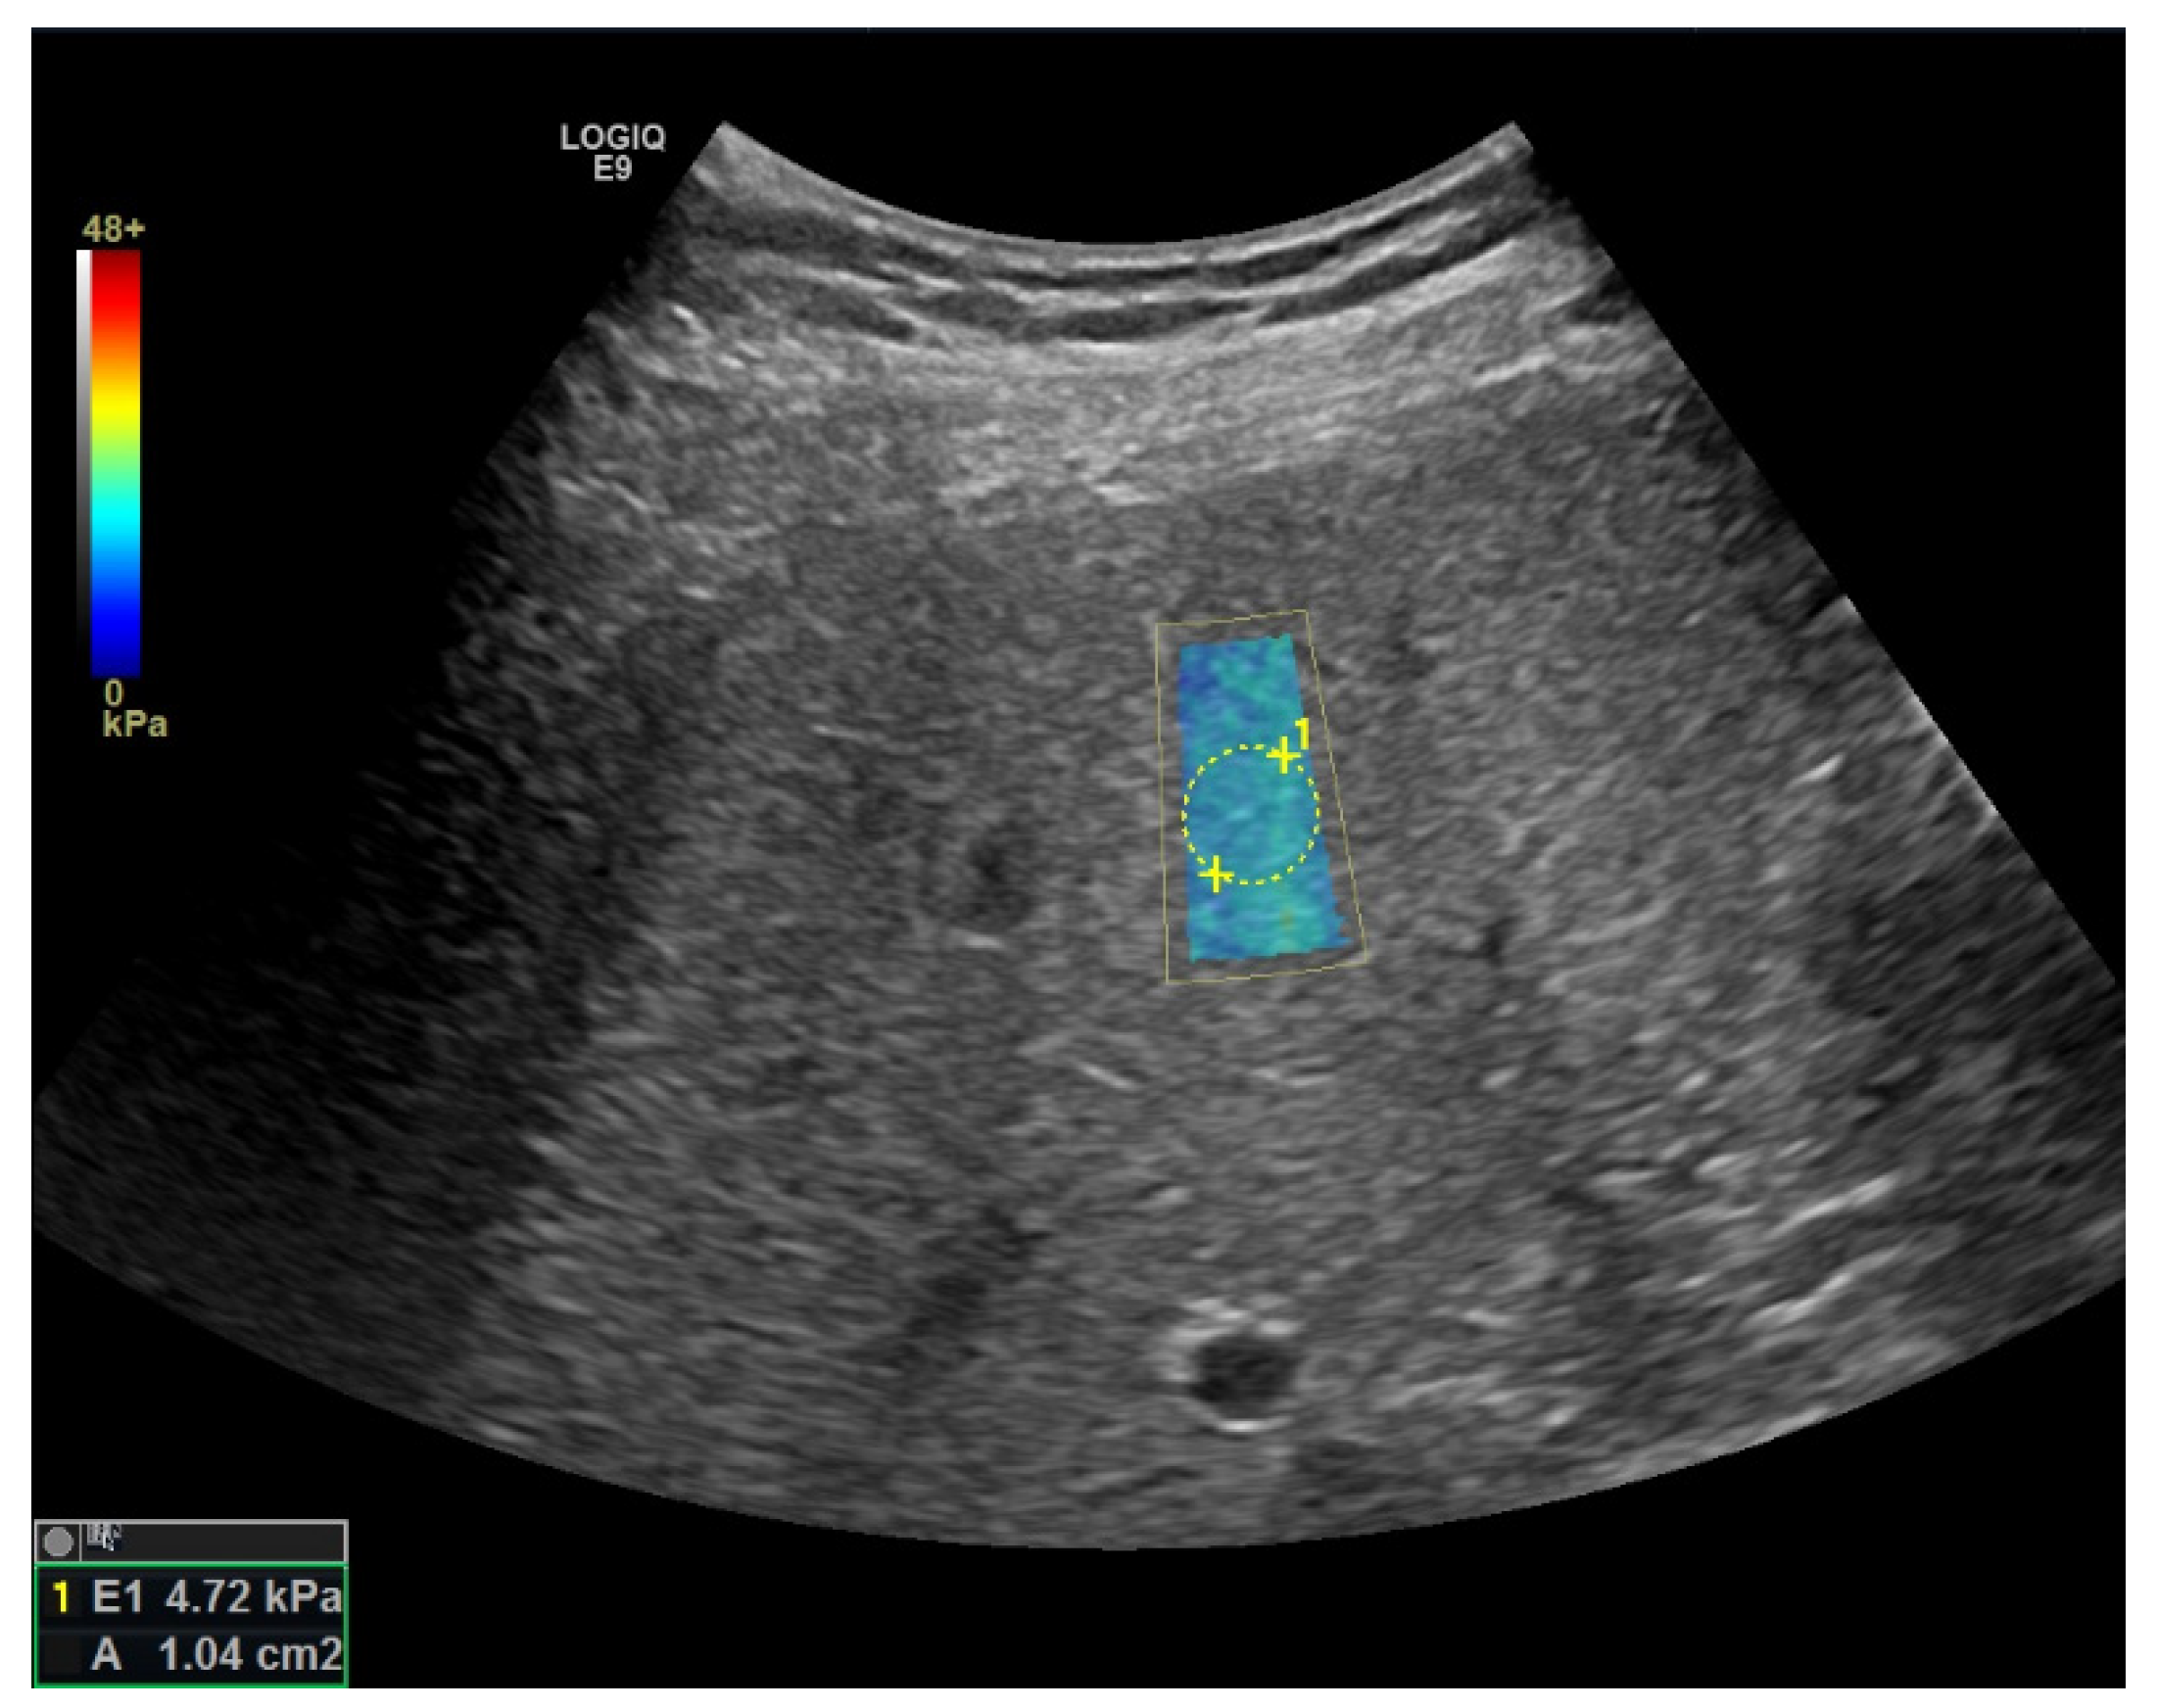

Elastography

| pSWE [41] | F ≥ 2: 69% F ≥ 3: 80% F = 4: 76% | F ≥ 2: 85% F ≥ 3: 86% F = 4: 88% | -integrated in high-end devices, performing in combination with regular US | -smaller ROI |

| 2D-SWE [41] | F ≥ 2: 71% F ≥ 3: 72% F = 4: 78% | F ≥ 2: 67% F ≥ 3: 72% F = 4: 84% | -integrated in high-end devices, performing in combination with regular US -larger ROI (potential more representative) | -high failure rate in obese patients -lack of studies for most devices -lack of defined quality criteria |